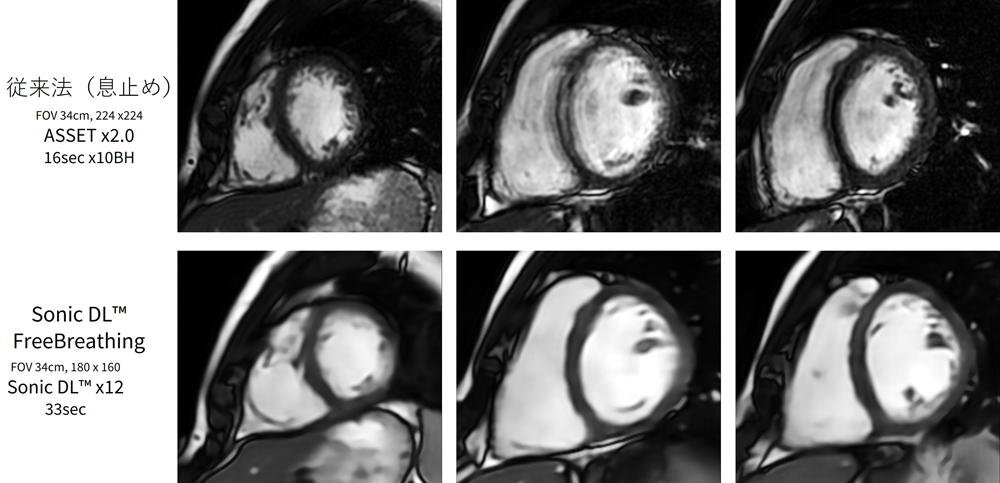

Sonic DL™はディープラーニングによる心臓Cineの高速撮像法で,画質を損なわずに短時間撮像を行うための画像再構成技術である。従来の高速撮像技術であるパラレルイメージングや圧縮センシングは,高速化により信号雑音比(SNR)の低下や画質の劣化を伴う。Sonic DL™は空間軸と時間軸に対して畳み込み演算を行うディープラーニングアルゴリズムにより,高いアクセラレーションファクターでも画質を損ねることなく,撮像の高速化と画質の両立を実現したCine撮像が可能になる。各時相あたりの時間分解能は,アクセラレーションファクターと1スライスあたりの心拍数の設定によって設定される。当院では,アクセラレーションファクター10倍,1スライス当たり3心拍でCine撮像を行っている(Figure.1)。Sonic DL™は最大12倍のアクセラレーションファクターの設定が可能で,患者の状態に応じて,1スライスあたり1心拍での高速撮像も可能である。また呼吸同期との併用で自由呼吸下でのCine撮像を行うことも可能であり,あらゆる臨床場面に対応できる高速撮像技術である。

SonicDL_Iwateikadai03.jpg

Figure.1 従来法とSonic DL™によるCine撮像の比較

従来当院では,スライス毎の息止めで心臓Cineを撮像していた。このためインターバルで呼吸を整える時間を含めると,短軸像だけで平均5分30秒程度の時間を要していた。一方Sonic DL™による心臓Cine撮像では,1-3回の息止めで短軸像を取得することが可能である。高い画質を維持しながら,撮像時間はインターバルを含めても平均1秒30秒程度にまで短縮する(Figure.1)。さらに長軸像を含めても,3分以内で心臓Cine撮像を完了することが可能である。撮像時間の短縮や息止め回数の削減は,検査時間の短縮のみならず,患者負担が大幅に軽減される。Sonic DL™の導入で息止め不良に伴う画質低下のリスクが減少し,安定したCine画像が得られるようになった。